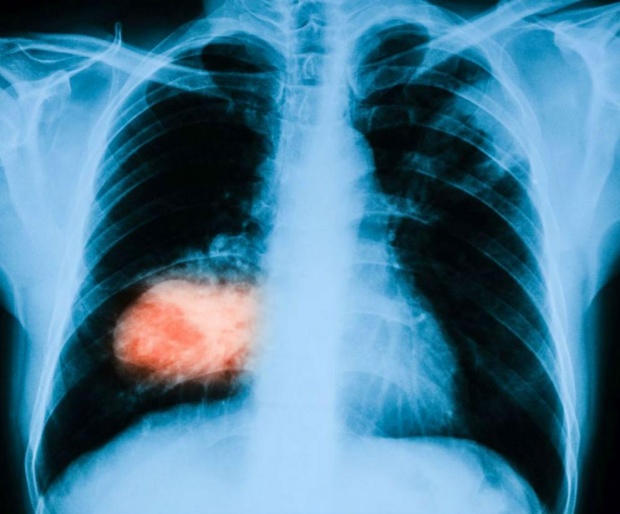

Сингапурски специалисти са разработили и тествали нова процедура, която помага на лекарите с по-голяма лекота и точност да откриват белодробен рак, пише в. "Стрейтс таймс".

Постижението им може да доведе до по-ранна диагностика и лечение на злокачествено заболяване на органа.

Наречена навигационна бронхоскопия, процедурата комбинира виртуална реалност и GPS проследяване, за да открива и извлича предполагаеми ракови клетки в белия дроб. Методът вече е изпробван в местна болница без усложнения върху 33 пациенти.

При процедурата се създава триизмерна "пътна карта", предлагаща няколкото възможни маршрута, по които лекарят може да поеме, за да установи местонахождението на предполагаемите ракови клетки. Веднъж достигнато точното място, тъканите се извличат със съответните инструменти за биопсия.

Методът намалява риска, съпътстващ стандартните биопсии при белодробен рак, който най-често се обуславя именно от липсата на подобна навигационна карта.